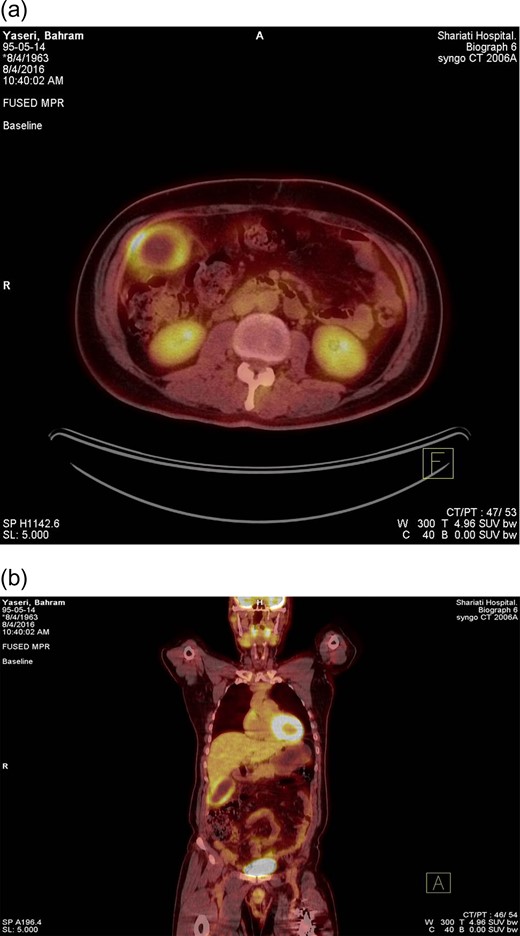

A 53 years old man with a history of large bowel obstruction secondary to a sigmoid mass had undergone urgent sigmoid resection and colon anastomosis about 12 months earlier. Histopathologic survey demonstrated sigmoid adenocarcinoma. Thus, he received eight courses of adjuvant chemotherapy. Tumor marker was within the normal range at the end of treatments. During surveillance, carcinoembryionic antigen (CEA) level slightly elevated along with new symptoms of upper abdominal pain; although CT imaging from the chest, abdomen and pelvis revealed no remarkable abnormal finding except a small gall stone. The patient was referred for FDG PET-CT to detect possible recurrence or metastasis. On FDG PET-CT study, no clear evidence in favor of residual or metastatic disease was identified; however, the gallbladder was distended and located in an unusual position. The gallbladder contained small stones accompanied with mural calcification in the neck. Gallbladder wall thickening was also seen demonstrating a ring like pattern of increased FDG uptake with SUVmax = 6.5. These findings were interpreted as acute/chronic cholecystitis (Fig. 1). On the basis of this interpretation, the patient was referred back for cholecystectomy. After the operation, he was clinically improved and 8 weeks later the serum CEA level came back to normal range. Histopathologic examination was compatible with acute on chronic cholecystitis confirming FDG PET-CT result. In long-term follow up, CEA is within normal values with no evidence of recurrence till February 2019 (Table 1).

FDG PET-CT with (a) trans-axial and (b) coronal views. PET-CT scan performed to evaluate a patient with colon cancer interfacing mild rise in blood CEA level. One hour after the intravenous administration of 11 mCi of 18 F-FDG, PET-CT images were obtained. A strikingly enlarged gallbladder shows intense radiotracer uptake in the gallbladder wall with a central photopenic area representing a rim like pattern. Metabolically active wall proposes the possibility of cholecystitis (acute/chronic). The patient underwent laparoscopic cholecystectomy. The histopathologic evaluation confirmed imaging findings as acute on chronic cholecystitis. Two months following surgical intervention, the CEA level declined to the normal range.